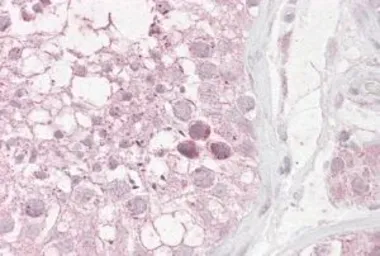

RNF36 antibody, C-term

Cat. No. GTX89832

ApplicationsWB IHC-P